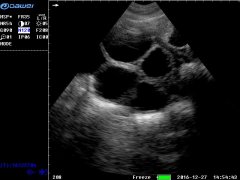

高危胎兒診治技術_雙胎妊娠超聲檢查技術規范

雙胎超聲檢查量亦呈上升趨勢, 據該項目組中具有代表性的中國醫科大學附屬盛京醫院統計: 2016年雙胎超聲檢查人次數(5235人次)是2013年 (1917人次)...